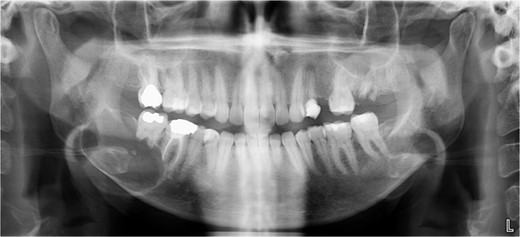

A 40-year-old woman presented with swelling on the right side of her mandible. She had completed orthodontic treatment 2 years earlier. A panoramic radiograph showed a unilocular radiolucency extending from the mandibular angle to the right first molar region (Figs 1–3).

Panoramic radiograph showing a unilocular radiolucency extending from the right mandibular angle to the right first molar region.